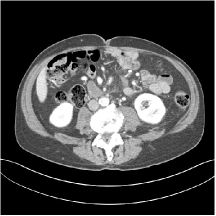

III.C.2. Simulation Framework, Reconstruction Results, and Comparisons

The synthesized low-dose clinical measurements are simulated from regular-dose images at a resolution of mm with a fan-beam CT geometry corresponding to a monoenergetic source at incident photon intensity . The sinograms are of size . The width of each detector column is mm, the source to detector distance is mm, and the source to rotation center distance is mm. We reconstruct images of size with the pixel size being mm mm.

We conducted experiments on one test slice used for parameter tuning (L067-slice 120) and four independent test slices (L109-slice 90, L192-slice90, L333-slice140, L506-slice 100) of the Mayo Clinic data. For PWLS-EP, we ran iterations using relaxed OS-LALM and set regularization parameter . We used the same as the phantom experiments for Algorithm 2. The process of selecting a general set of reconstruction parameters () for the Mayo Clinic test slices is identical to that for the XCAT phantom in Section III.B.2. The selected regularization parameter and the parameters that control the sparsity of the coefficient maps are for ST, , , , , for MARS2, , , , , , , for MARS3, , , , , , , , , , , for MARS5, and , , , , , , , , , , , , , , for MARS7, respectively.

Figs. 8, 9, 10, and 11 show the reconstructions of the four independent slices using the FBP, PWLS-EP, PWLS-ST, PWLS-MARS2, PWLS-MARS3, PWLS-MARS5, and PWLS-MARS7 schemes, respectively. Additional Mayo Clinic experimental results of the parameter tuning case (Fig. 15) are shown in the supplementary document. Table 1 lists the RMSE and SSIM values of reconstructions of the four independent test slices, with the best values bolded. Generally, the five and seven layer models provided the best RMSE and SSIM values. They outperform the single-layer model by HU in RMSE on average. However, the MARS5 and MARS7 models perform similarly. In order to strengthen the benefits of the multi-layer model, Table 2 lists the RMSE of the reconstructions in four different ROIs (shown in the reference of Fig. 11) with seven methods for slice 100 of patient L506. By observing the reconstructed images, we see that although the ST model achieves a cleaner reconstruction result than FBP and PWLS-EP, it still sacrifices some sharpness of the central region and suffers from loss of details. The deeper models have a somewhat more positive effect in terms of maintaining subtle features, which is clearly more essential to clinical diagnosis. Furthermore, as we will discuss later, after considerable parameter tuning, we found that the information contained in residual maps is gradually decreased with the number of layers, eventually vanishing at some layer, which suggests that very deep unsupervised models might not offer significantly better image quality.